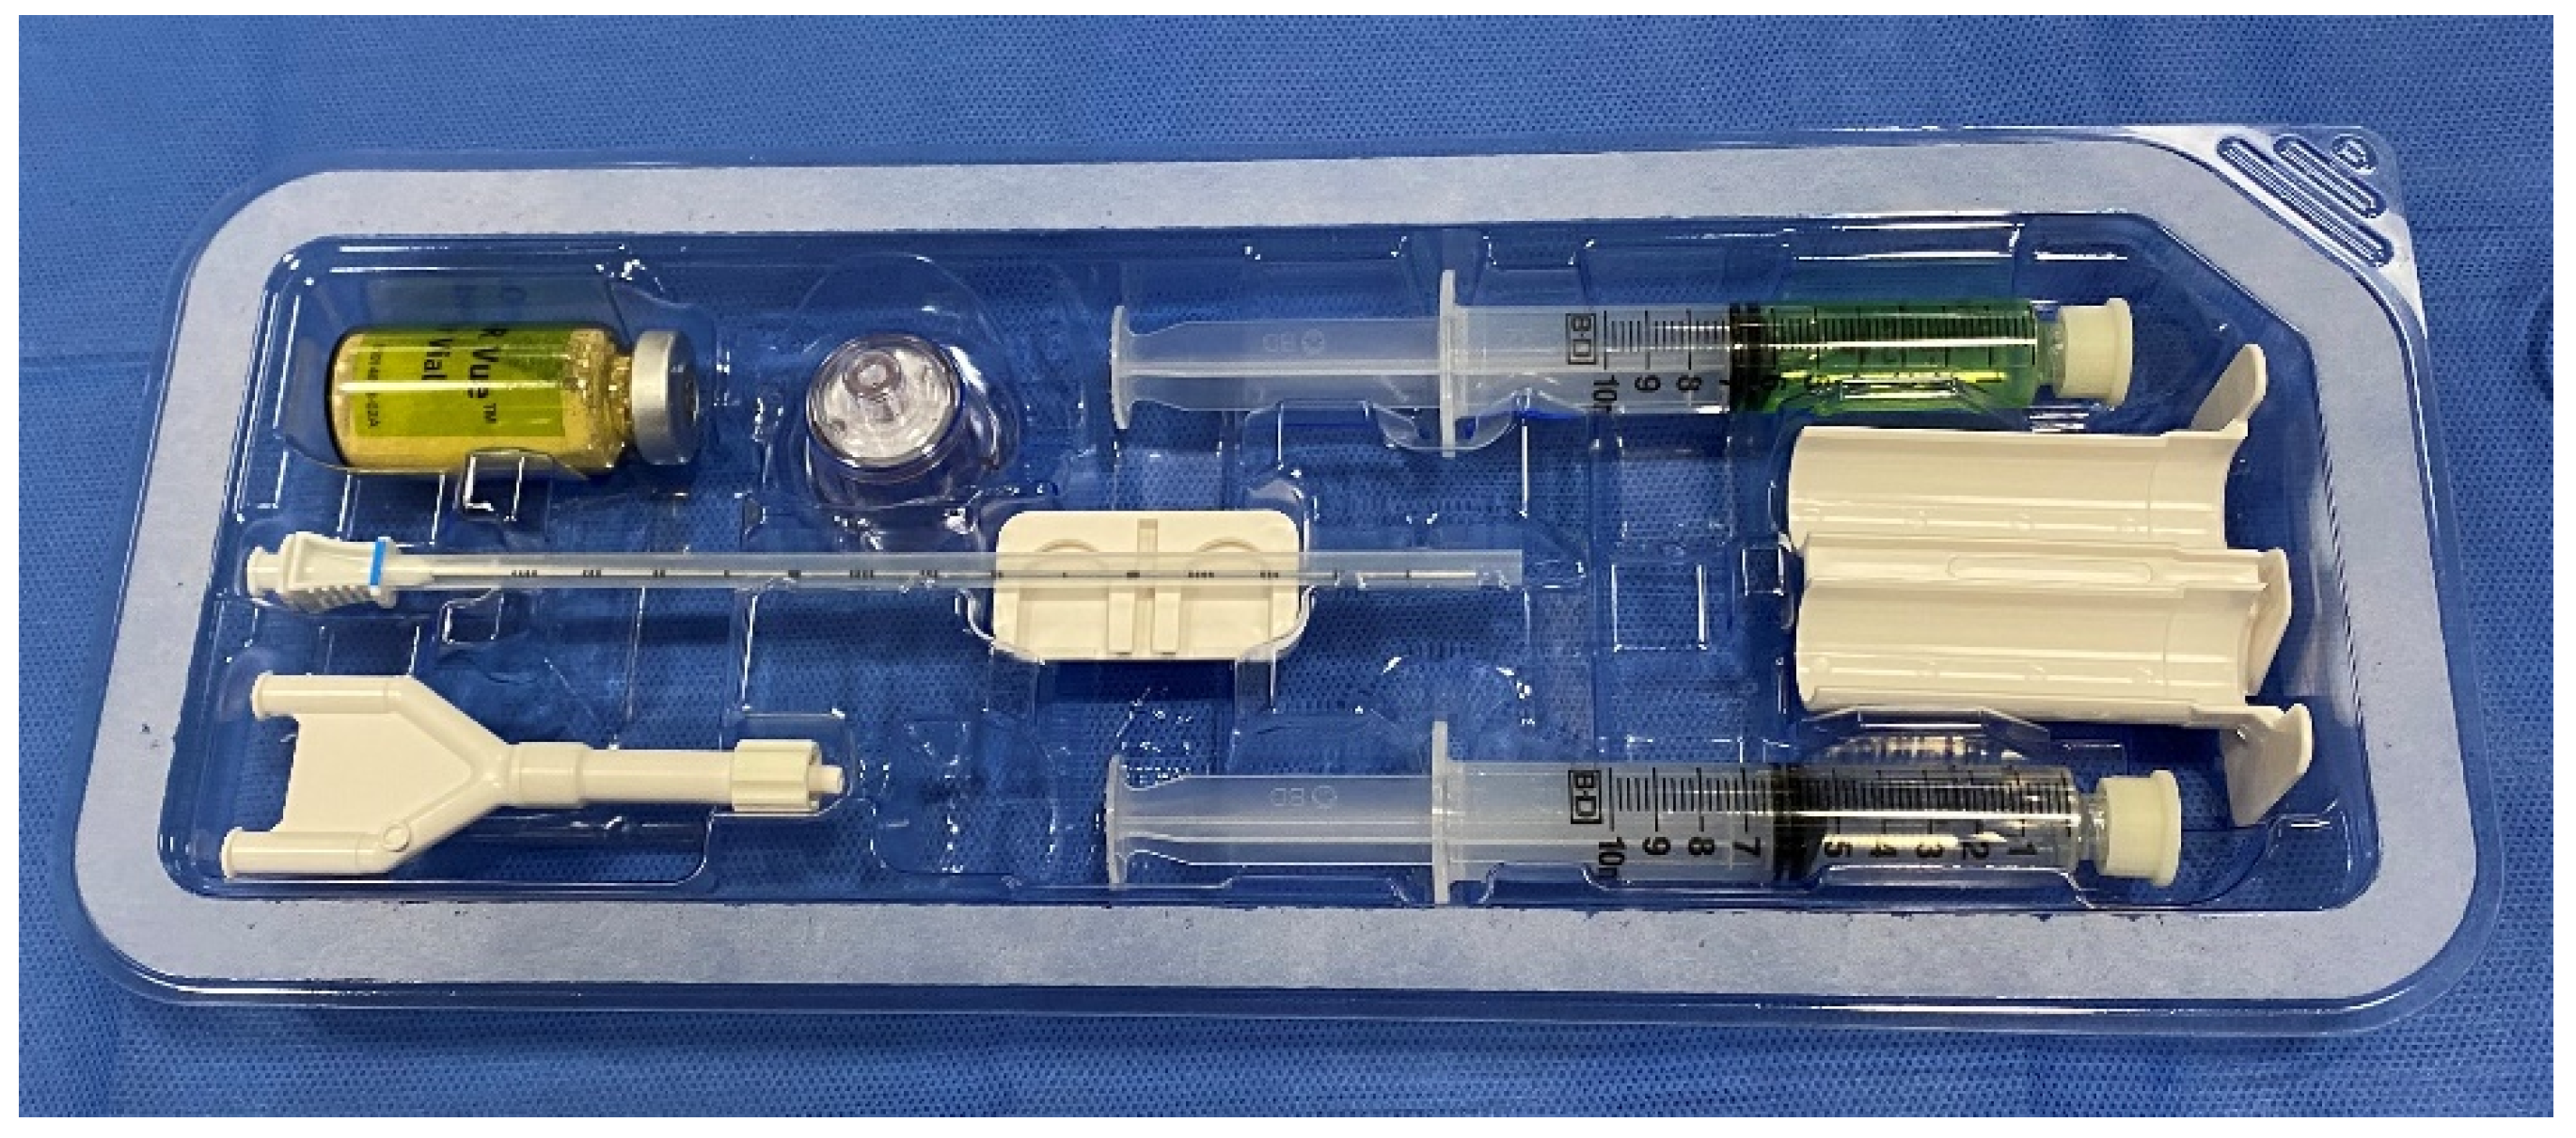

6. Placement

- SpaceOAR™ Vue System. 2022. Available online: https://www.bostonscientific.com/content/dam/bostonscientific/spaceoar/vue/URO-855204-AA%20SpaceOAR%20VUE_Brief%20Summary.pdf (accessed on 9 August 2022).

- SpaceOAR Vue™ Hydrogel. 2020. Available online: https://www.bostonscientific.com/content/dam/bostonscientific/spaceoar/vue/SpaceOAR-Vue-Hydrogel-Brochure.pdf (accessed on 9 August 2022).